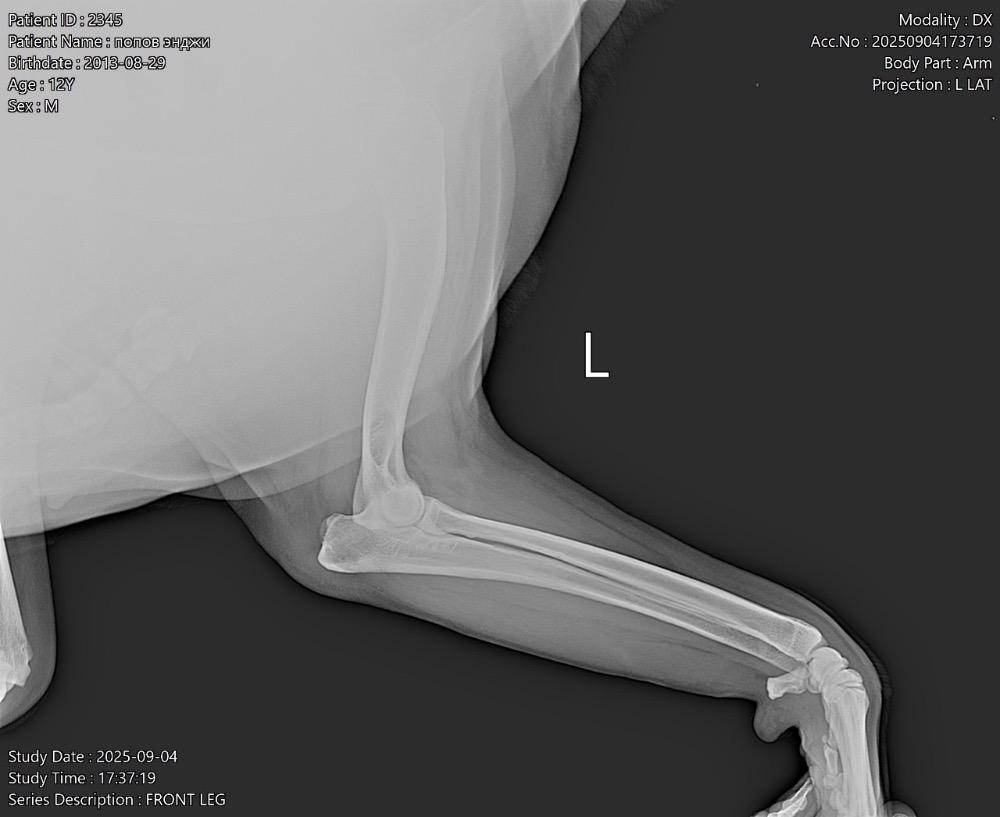

Татьяна13 Опубликовано 24 ноября, 2025 Опубликовано 24 ноября, 2025 (изменено) Всем здравствуйте! В июне началась проблема с лапами. Поставили диагноз-остеоартрит! Робексера+пк мерц прекрасно справлялись! На прошлой неделе собаке резко стало худо. Она начала часами без остановки дышать, иногда пристанывая. Было ясно, собаку что-то беспокоит…. В ветеринарке сдали анализ крови, сделали узи брюшной полости-ничего критичного… Врач решил, что Робексера уже не помогает, заменили на Фироко 227 мг + также оставили пк мерц. Добавили усросан, чтоб чуть полечить печень, так как небольшие отклонения есть… За 3 дня улучшений не вижу. Собака все также дышит без остановки часами, иногда пристанывая, второй день отказывается от корма (но вкусняшки ест), воду из миски пить отказывается (но пьет в ванной из душа и ест снег). Сегодня как будто начали отказывать задние лапы-она волочит ими. Вновь погнали в ветеринарку, они настаивают, что Фироко препарат хороший, сильнее его уже нет. Ждите! Чего ждать? Обезболивающее должно действовать же сразу…. Сказали, что тут скорее всего произошло защемление позвонка! Поэтому задние лапы не слушаются! И либо опять же ждите, либо делайте мрт, а потом операцию (собаке без пяти минут 12 лет, кстати!). Вдобавок выписали: Габапентин. В четверг хотят еще прокапать Хиовет. Сейчас, солнце мое спит, ходить не может. Когда просыпается, пытается встать и начинает дико плакать! И снова ложится! Люди, чем помочь собаке моей? Столько таблеток выписали… Как не навредить😭 У меня уже сердце болит… Изменено 24 ноября, 2025 пользователем Татьяна13 1